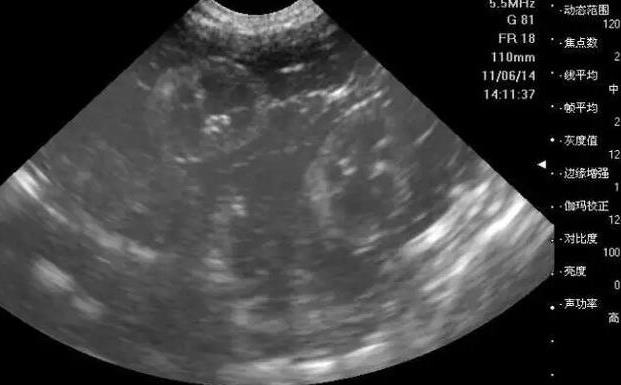

3. 卵泡監測:在促排卵治療期間,醫生會通過超聲波監測女性的卵泡情況,以確定最佳的取卵時間。